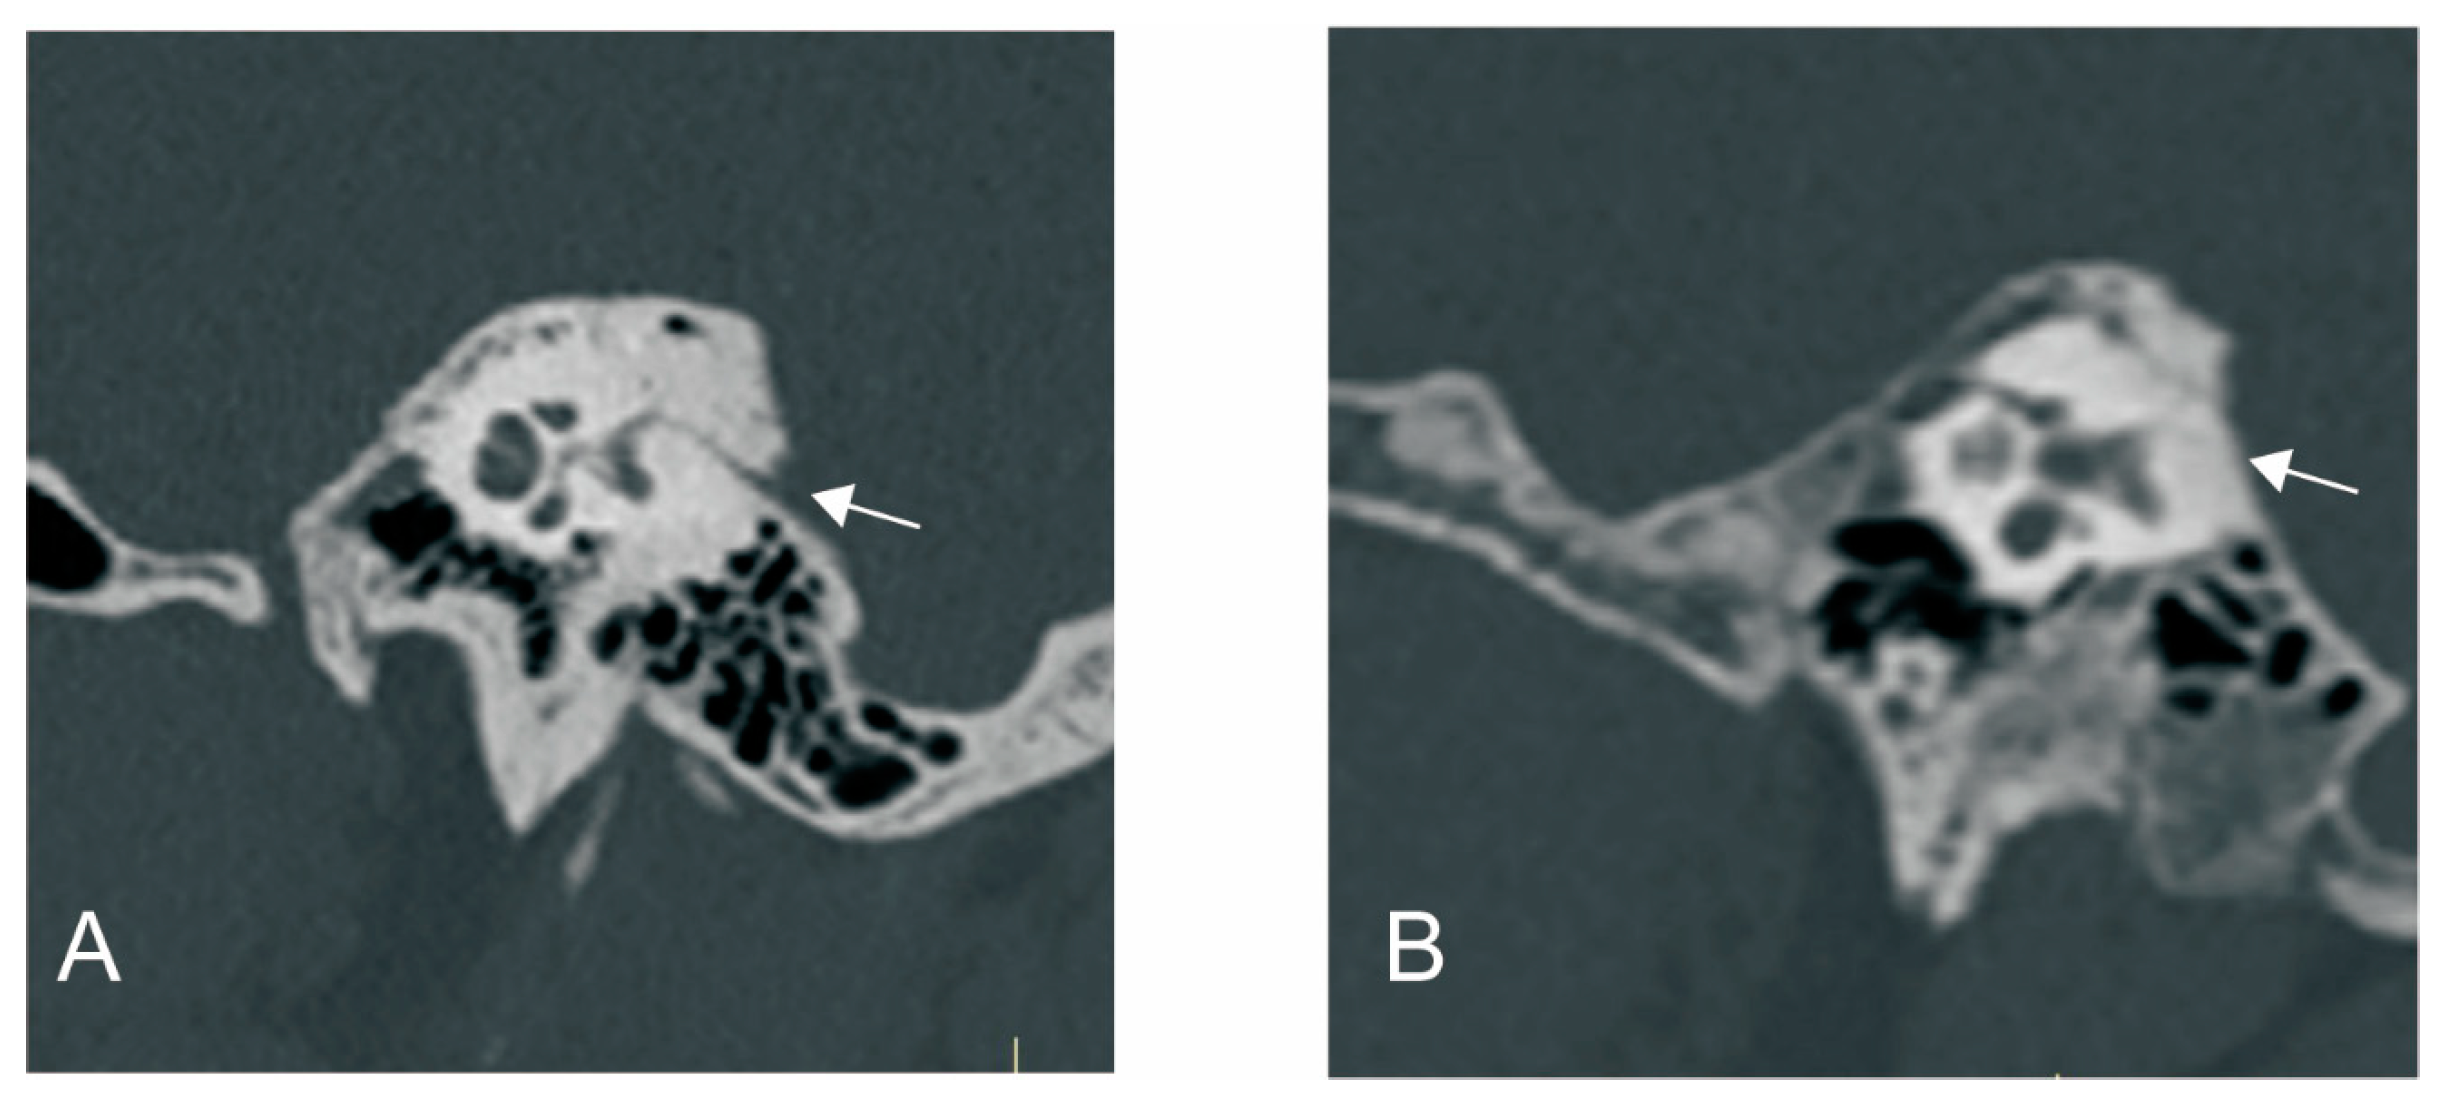

The visibility of VA in HRCT was graded as previously reported [9]: grade 0, continuous VA; grade I, discontinuous VA; grade II, invisible VA (Figure 1).

Figure 1.

The grading of vestibular aqueduct (VA) visibility on the 45° oblique (Pöschl) planes on temporal bone CT. (A) Grade 0 with a continuous VA. (B) Grade I with a discontinuous VA. White arrow: VA.